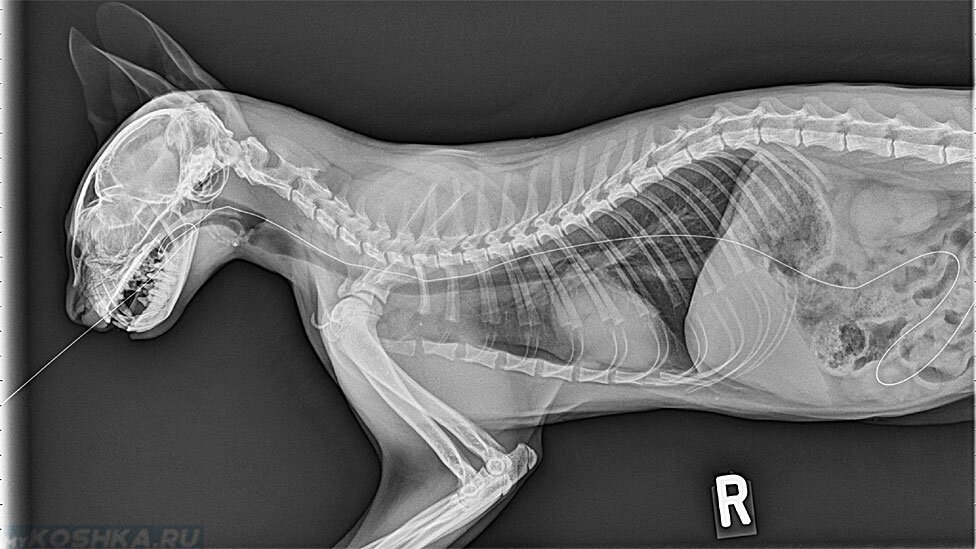

Рентген Задней Лапы Кошки: Нормы и Диагностика